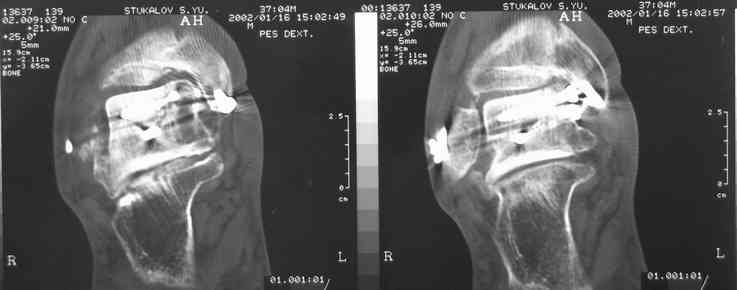

Имя     : кт после остеосинтеза.jpg

Тип     : image/jpeg

Размер  : 22374 байтов

Описание: отсутствует

Url     : http://weborto.net:8080/pipermail/ortho/attachments/20070616/4aa8531d/attachment-0006.jpg

В Вашей ситуации мы произвели открытую репозицию и фиксацию

металлоконструкциями. Все зажило первично, посттравматического

дефартроза избежать не удалось. Пациент от артродезирующих операций в

отдаленном периоде отказался.